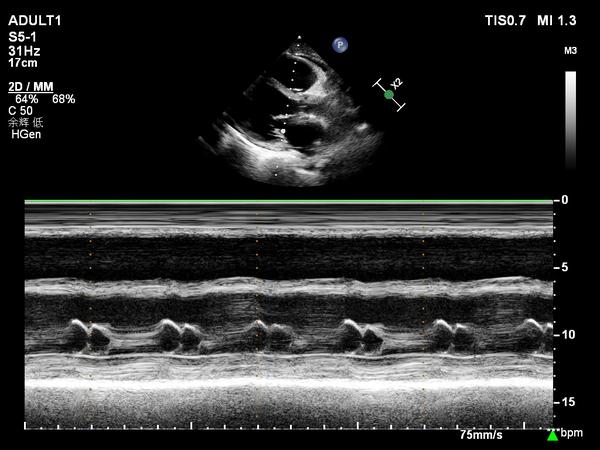

m型超声心动图